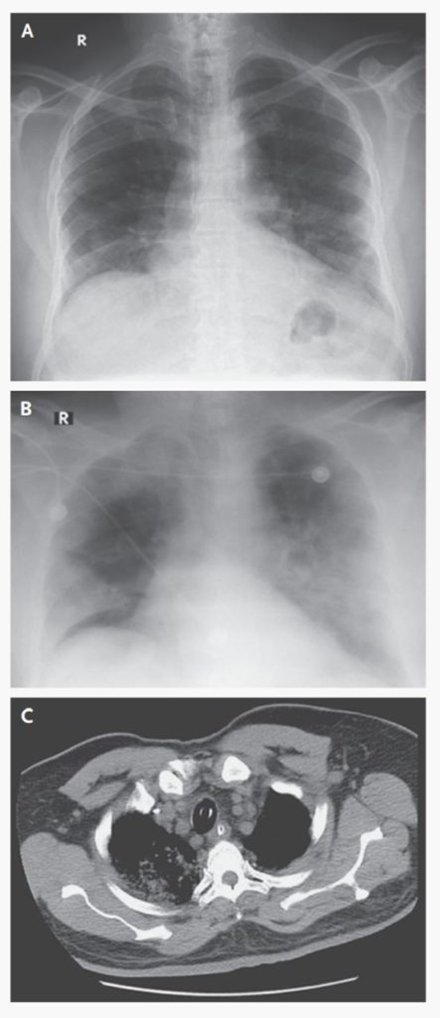

عينة السارس السعودية

في 13 يونيو 2012، أدخل رجل سعودي يبلغ من العمر 60 عاما إلى مستشفى خاص في جدة، المملكة العربية السعودية، يشكو من الحمى والسعال وضيق في التنفس لمدة 7 أيام. لم يكن لديه تاريخ أمراض قلب ورئة أو كلى، ولم يكن يتلقى أي أدوية طويلة الأجل، ولم يكن يتتن.

2.4

عزل عالم الفيروسات المصري الدكتور علي محمد زكي وتعرف على فيروس تاجي لم يكن معروفا من قبل من رئتيه. بعد فشل التشخيص الروتيني في تحديد العامل المسبب، اتصل زكي برون فوشييه، عالم الفيروسات الرائد في مركز إيراسموس الطبي (EMC) في روتردام، هولندا، للحصول على المشورة.

تم عزل فيروس كورونا غير معروف سابقا من بلغم رجل 60 عام أصيب بالتهاب رئوي حاد وفشل كلوي لاحقا مع نتيجة قاتلة في السعودية.

بسهولة في زراعة الخلايا ، مما ينتج عنه تأثيرات اعتلال خلوي للتقريب والانفصال وتكوين المخلوقات. يمثل الفيروس نوع جديد من فيروس بيتاكورونا. أقرب الأقارب المعروفين هم فيروسات الخفافيش التاجية HKU4 و HKU5. هنا ، يتم تقديم البيانات السريرية وعزل الفيروس والتعرف الجزيئي.

كانت الصورة السريرية مشابهة بشكل ملحوظ لتلك الخاصة بتفشي مرض الالتهاب الرئوي الحاد (سارس) في عام 2003 وتذكرنا بأن فيروسات كورونا الحيوانية يمكن أن تسبب مرضًا شديدًا لدى البشر.